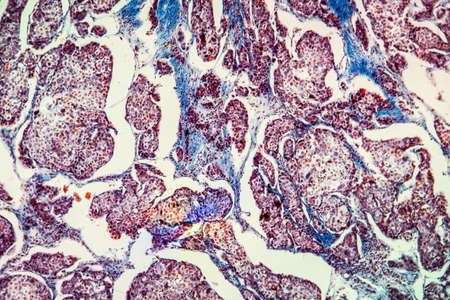

Bowen's Disease Tumor under the microscope 100x

Bowen's Disease Tumor under the microscope 100x